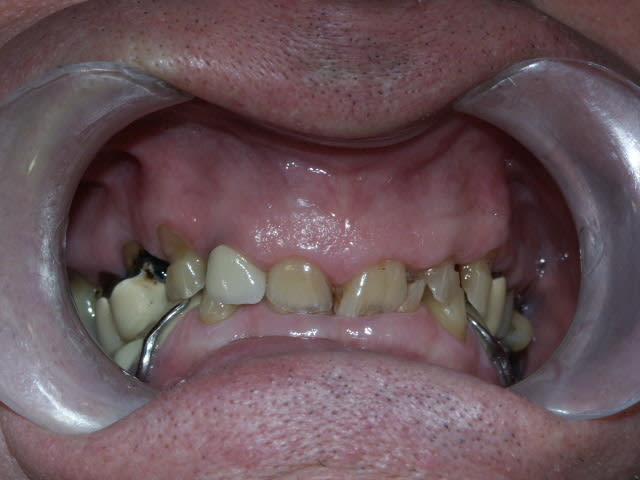

Qu'est ce que je peux proposer comme plan de traitement?

j'avoue que je suis un peu paumé...

le stellite a été fait sur ce patient de 68 ans il y a moins d'un an.

tout à fait. C'est un monsieur charmant de 68 ans. Il vient pour voir ce qu'on peut faire, pas le genre à être un chiant, du tout. Il est conscient de son problème et de la difficulté à le traiter.

Le constat est le suivant, corrigez-moi si je me trompe:

on a eu des extractions non compensées à la mandibule qui ont provoquées des égressions des dents maxillaires postérieures.

une abrasion +++ du bloc antérieure avec égression "physiologique" au fur et à mesure de l'usure.

On a ainsi un décalage important (comme une marche d'escalier) de la courbe d'occlusion (Spee) entre le secteur antérieur et postérieur.

La difficulté de la thérapeutique consistera à rattraper le mieux possible ce décalage pour avoir une courbe d'occlusion "harmonieuse".

Il conviendrait d'augmenter la DV partout mais on risque de se retrouver avec les difficultés suivantes:

- en postérieur, l'augmentation de DV sera importante et on risque de vite se retrouver avec des couronnes avec un rapport couronne / racine défavorable.

- en antérieur, le gain de DV obtenu sera plus faible du fait de l'égression physiologique des dents. Le dilemne est de savoir si cela permettra d'avoir assez de place pour faire des couronnes.

Pour gagner un peu de hauteur sur les dents antérieures pour les futures CCM, je pensais faire des gingivectomies. Les bruxos ont souvent un parodonte en béton avec de la GA à revendre, favorable à cette technique. Cela permettrait de limiter l'augmentation de DV. Le seul truc qui coince c'est que le patient n'a pas des racines très longues.